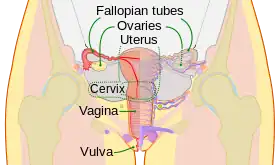

The human female reproductive system. The cervix is the lower narrower portion of the uterus. | |

The cervix (pl.: cervices) or cervix uteri (Latin, "neck of the uterus") is the lower part of the uterus (womb) in the human female reproductive system. The cervix is usually 2 to 3 cm long (~1 inch) and roughly cylindrical in shape, which changes during pregnancy. The narrow, central cervical canal runs along its entire length, connecting the uterine cavity and the lumen of the vagina.[1] The opening into the uterus is called the internal os, and the opening into the vagina is called the external os. The lower part of the cervix, known as the vaginal portion of the cervix (or ectocervix), bulges into the top of the vagina. The cervix has been documented anatomically since at least the time of Hippocrates, over 2,000 years ago.

The cervix is part of the female reproductive system. Around 2–3 centimetres (0.8–1.2 in) in length,[3] it is the lower narrower part of the uterus continuous above with the broader upper part—or body—of the uterus.[4] The lower end of the cervix bulges through the anterior wall of the vagina, and is referred to as the vaginal portion of cervix (or ectocervix) while the rest of the cervix above the vagina is called the supravaginal portion of cervix.[4] A central canal, known as the cervical canal, runs along its length and connects the cavity of the body of the uterus with the lumen of the vagina.[4] The openings are known as the internal os and external orifice of the uterus (or external os), respectively.[4] The mucosa lining the cervical canal is known as the endocervix,[5] and the mucosa covering the ectocervix is known as the exocervix.[6] The cervix has an inner mucosal layer, a thick layer of smooth muscle, and posteriorly the supravaginal portion has a serosal covering consisting of connective tissue and overlying peritoneum.[4]